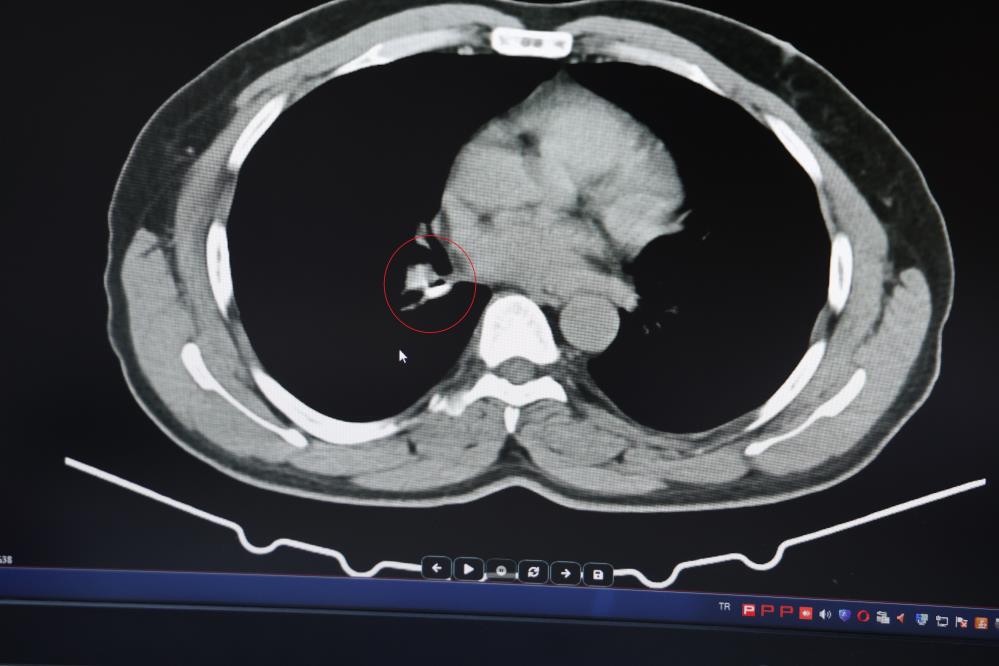

İ.U., Prof. Dr. Abdurrahman Şenyiğit’e başvurduğunda yapılan tetkiklerde, akciğere yerleşen maddenin yutulan silikon olduğu tespit edildi. Tomografi ve bronkoskopi ile doğrulanan bu bulgu sonrasında silikon çıkarıldı ve hastanın şikayetleri hızla ortadan kalktı.

Prof. Dr. Abdurrahman Şenyiğit, yapılan açıklamada, diş tedavilerinde kullanılan silikonlu materyalin akciğere kaçmasının hastada fark edilemeyecek şekilde uzun süre kalabildiğini belirtti. Şenyiğit, "Hastamıza maalesef 2 yıldan beri astım tanısı konulmuş ve sürekli tedavi verilmiştir. Hasta bize geldiği zaman yapılan tomografide sağ akciğer ana bronşun distalinde şüpheli lezyon gördük. Uyguladığımız bronskokopide yabancı maddenin silikon olduğunu tespit ettik. Onu çıkardıktan sonra da hastada bir rahatlama meydana geldi" ifadelerini kullandı.